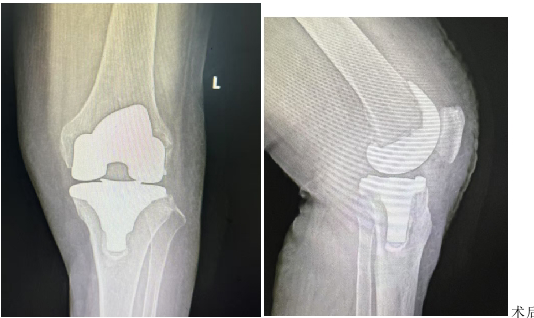

术后复查DR显示,人工膝关节对位良好,内固定位置理想。

【术后影像】